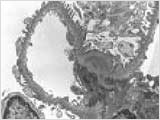

<»ç±¸Ã¼

½Å¿°ÀÇ Á¶Á÷°Ë»ç ¼Ò°ß>

±¤ÇÐ

Çö¹Ì°æ »çÁø ÀüÀÚ Çö¹Ì°æ

»çÁø ¸é¿ª

Çü±¤ »çÁø